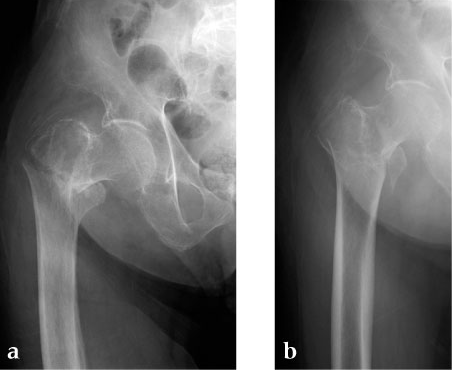

Case 3: 90-year-old male, injured by fall down.

Case provided by Toru Sato, Okayana, JP